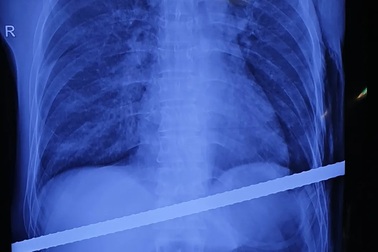

Kỳ tích cứu sống người đàn ông bị thanh sắt đâm xuyên ngườiKhông may bị ngã cầu thang do tai nạn lao động, nam bệnh nhân 42 tuổi bị thanh sắt đâm xuyên từ bờ dưới của sườn bên phải ngang qua người. Thanh sắt đâm xuyên qua gan, màng phổi bệnh nhân.